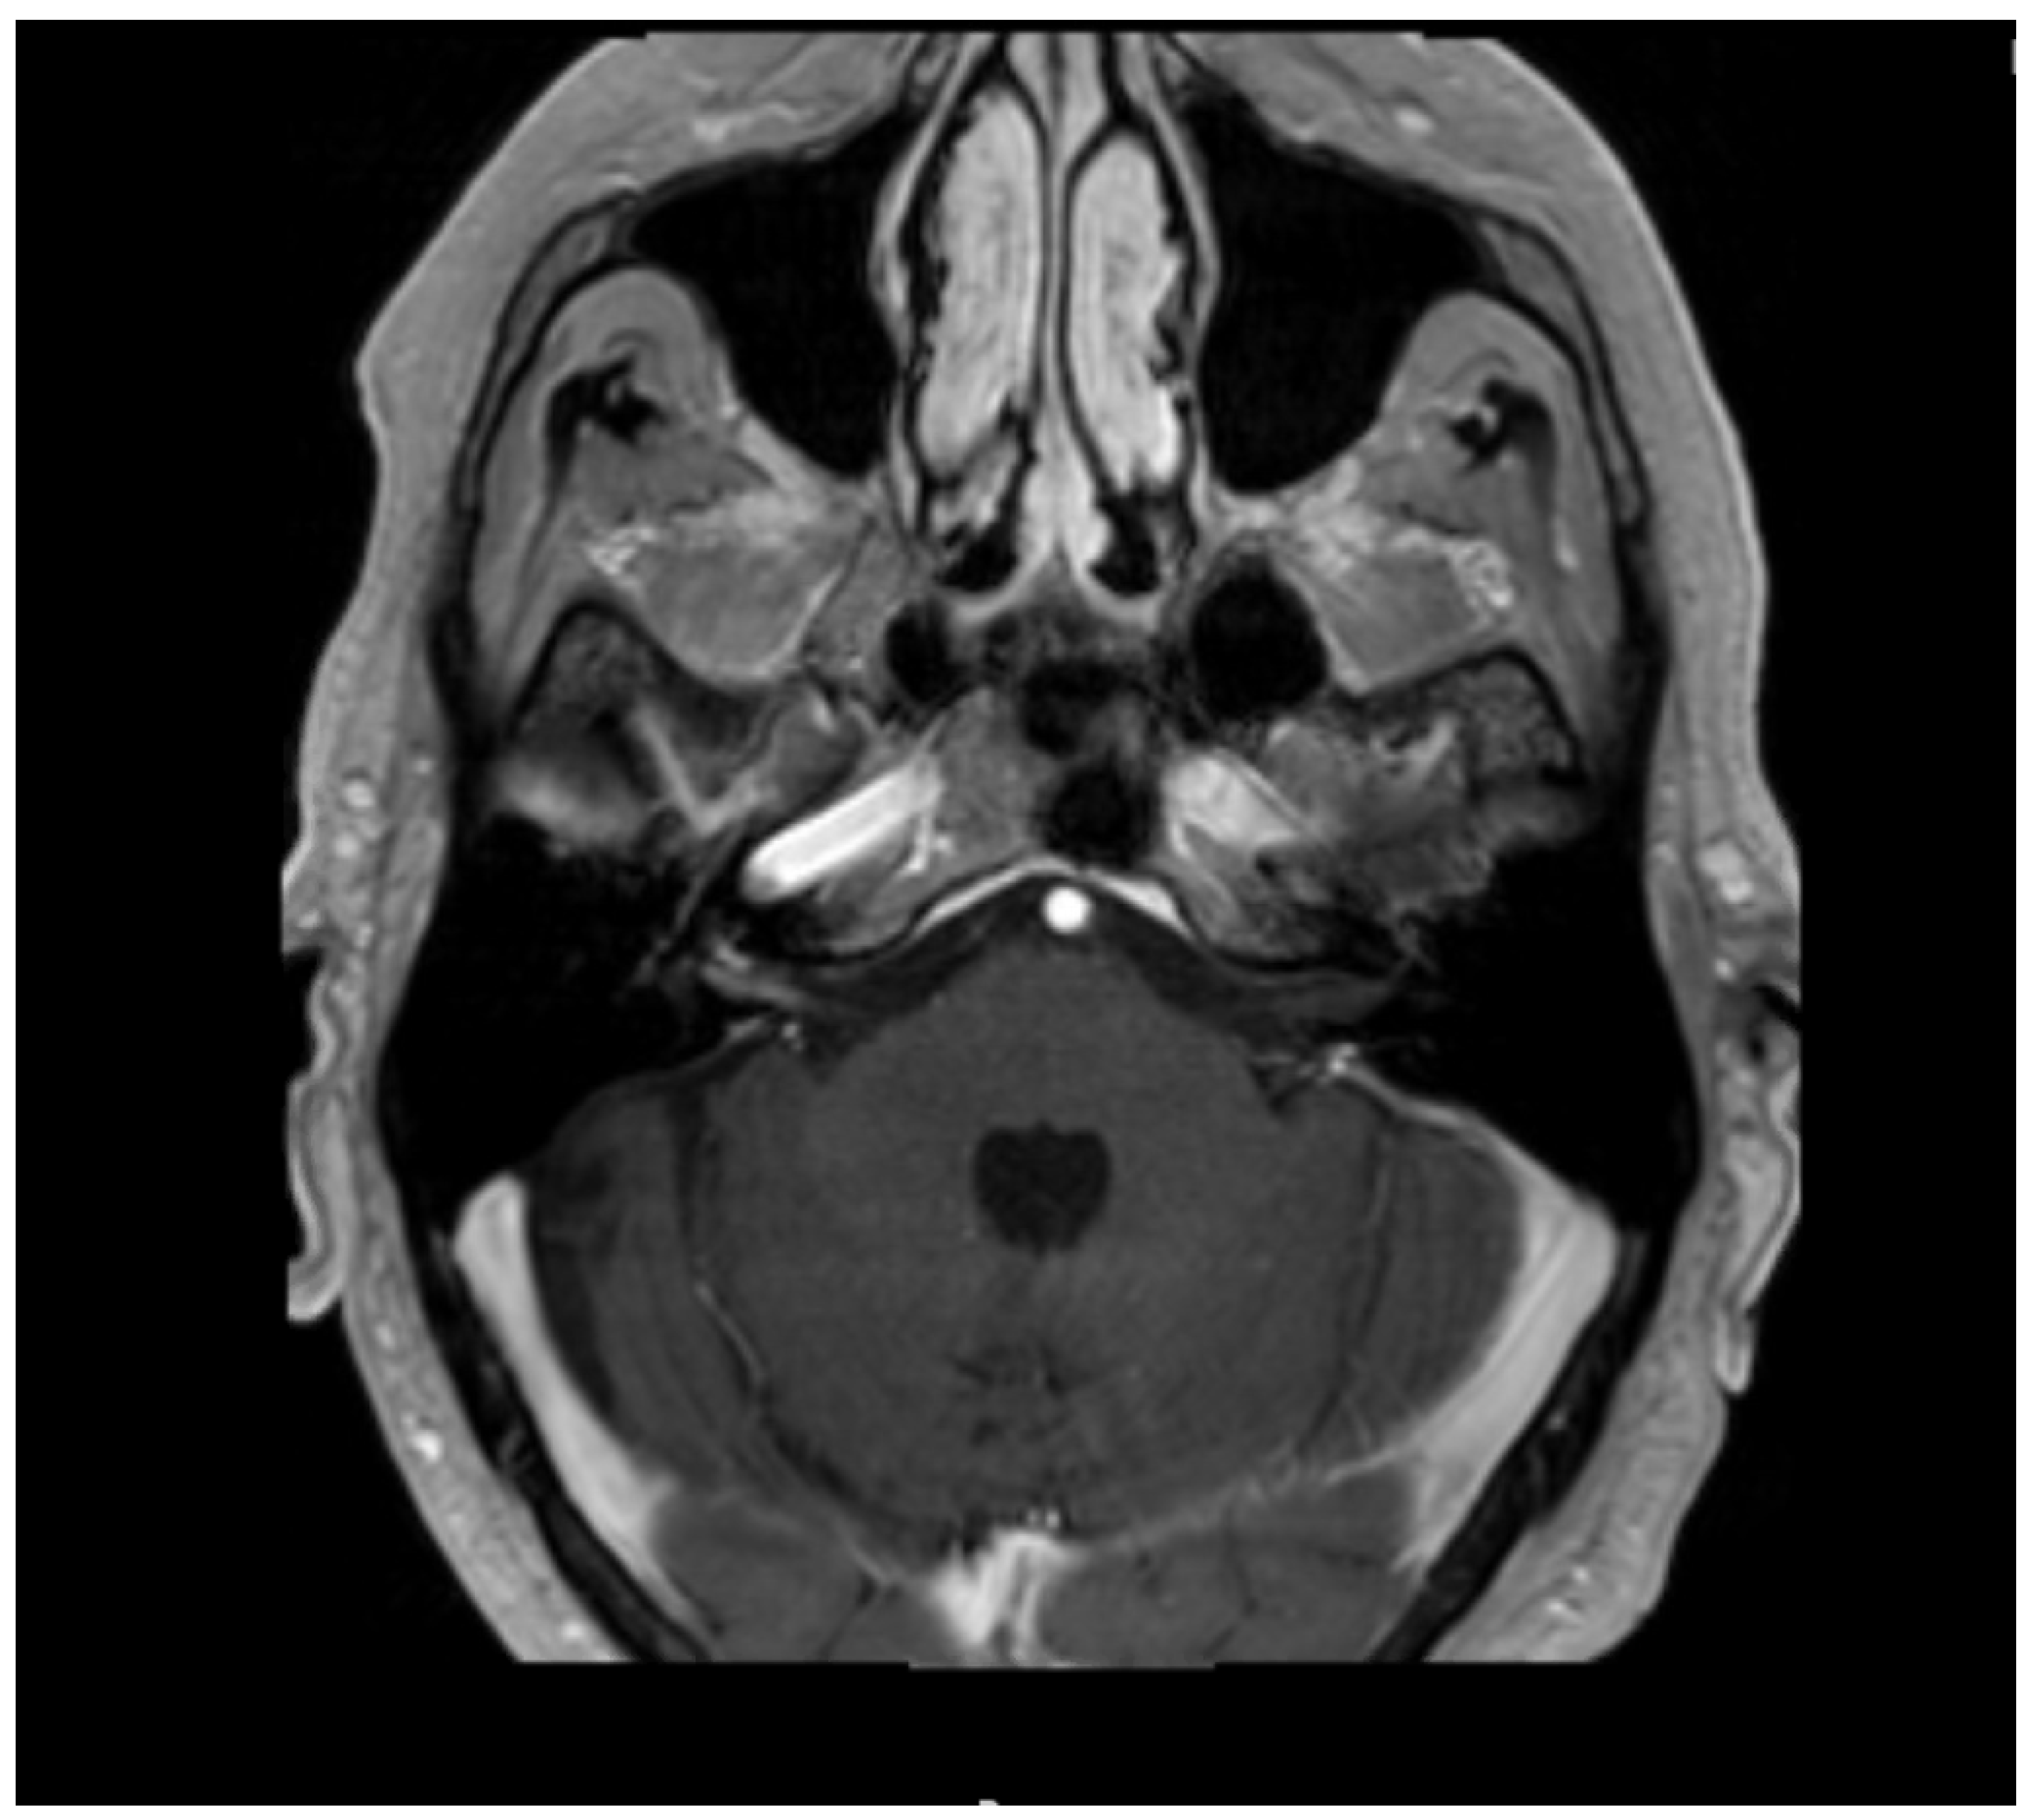

2. Case Presentation